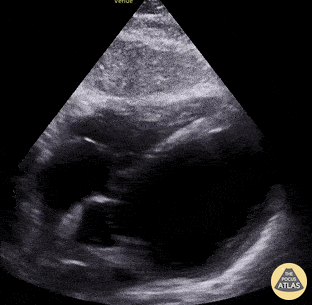

52-yo-male with PMH methamphetamine use presented with 1 month history of increasing DOE, orthopnea, and episodic atypical sharp chest pain. EKG revealed LVH with inferolateral T-wave inversions; troponin was indeterminate (making ACS less likely). POCUS demonstrated extremely reduced LVEF leading to a diagnosis of new systolic heart failure. Subsequent formal TTE demonstrated LVEF 10%; left heart cath revealed nonobstructive CAD. Final diagnosis of methamphetamine induced cardiomyopathy was made. Mike Heffler, MD Denver Health Emergency Medicine